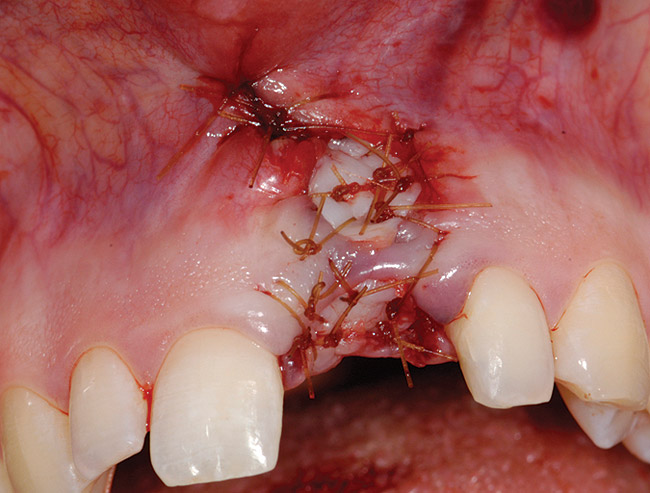

Treatment consisted of flapless extraction, socket grafting using mineralized bone allograft (Puros®, Zimmer Dental Inc, Carlsbad, CA), and a pedicled connective tissue graft36,37(Figure 11). Five months post-surgery, reentry was accomplished via a mid-crestal and labial sulcular incision. A crestal plasty was per- formed before implant placement into type II bone (Figure 12 and Figure 13). An immediate provisional was used for 3 months (Figure 14) before final crown fabrication (Figure 15).

Figure 13  Primary flap closure.

Figure 13